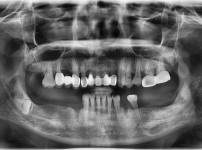

1

BEFORE

AFTER

클릭 해주세요.

하악 임플란트,치조골이식

임플란트